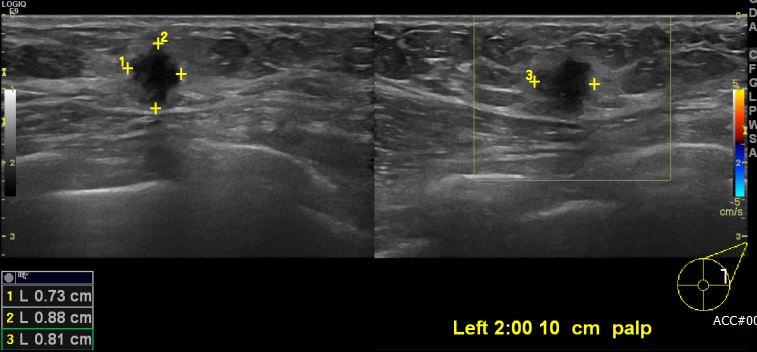

상기환자 좌측 유방에 만져지는 멍울로 내원하신 60대 여성분으로 좌측 2시

방향에서 10cm 떨어진 거리에 만져지는 멍울 조직검사 시행하여 좌측 침윤성

유관암 진단 되었습니다. 감사합니다.